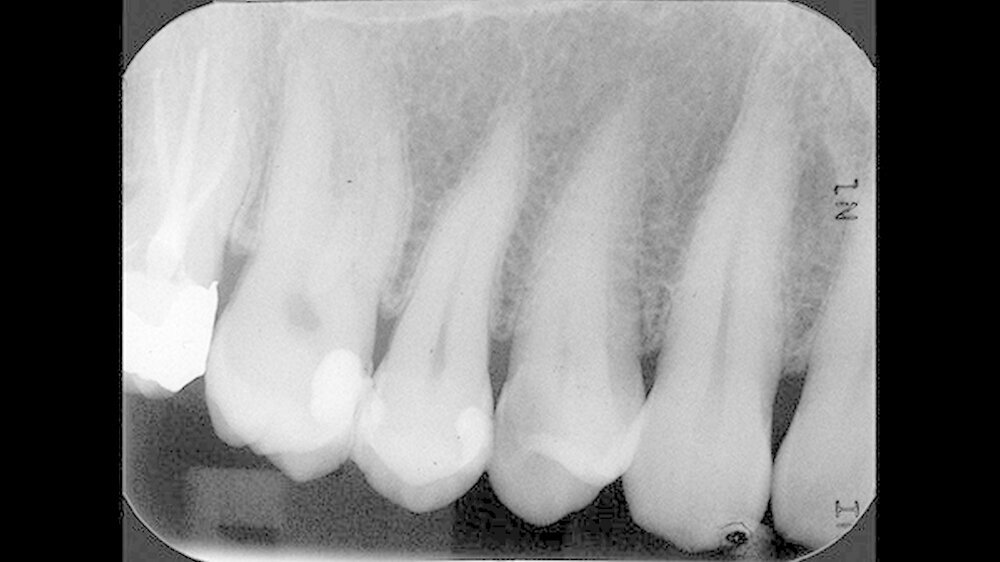

Ein 43-jähriger Patient stellte sich zur Routinekontrolle in der Poliklinik für Zahnerhaltung des Universitätsklinikums Münster vor. Die allgemeinmedizinische Untersuchung zeigte keine Besonderheiten. Sowohl der klinische zahnmedizinische Befund als auch die angefertigte Röntgenaufnahme deuteten auf eine Approximalkaries distal an Zahn 14 hin (Abbildungen 1 und 2). Daher wurde der Patient auf die Notwendigkeit einer Füllungstherapie hingewiesen.

Auf dem 26 Monate nach direkter Überkappung angefertigten Zahnfilm konnten apikal an Zahn 14 keine pathologischen Veränderungen festgestellt werden (Abbildung 12). Dem Patienten zufolge war es zu keinem Zeitpunkt, zum Beispiel im Kontakt mit kalter Nahrung, Flüssigkeit oder Luft, nach der direkten Überkappung zu Beschwerden an Zahn 14 gekommen.